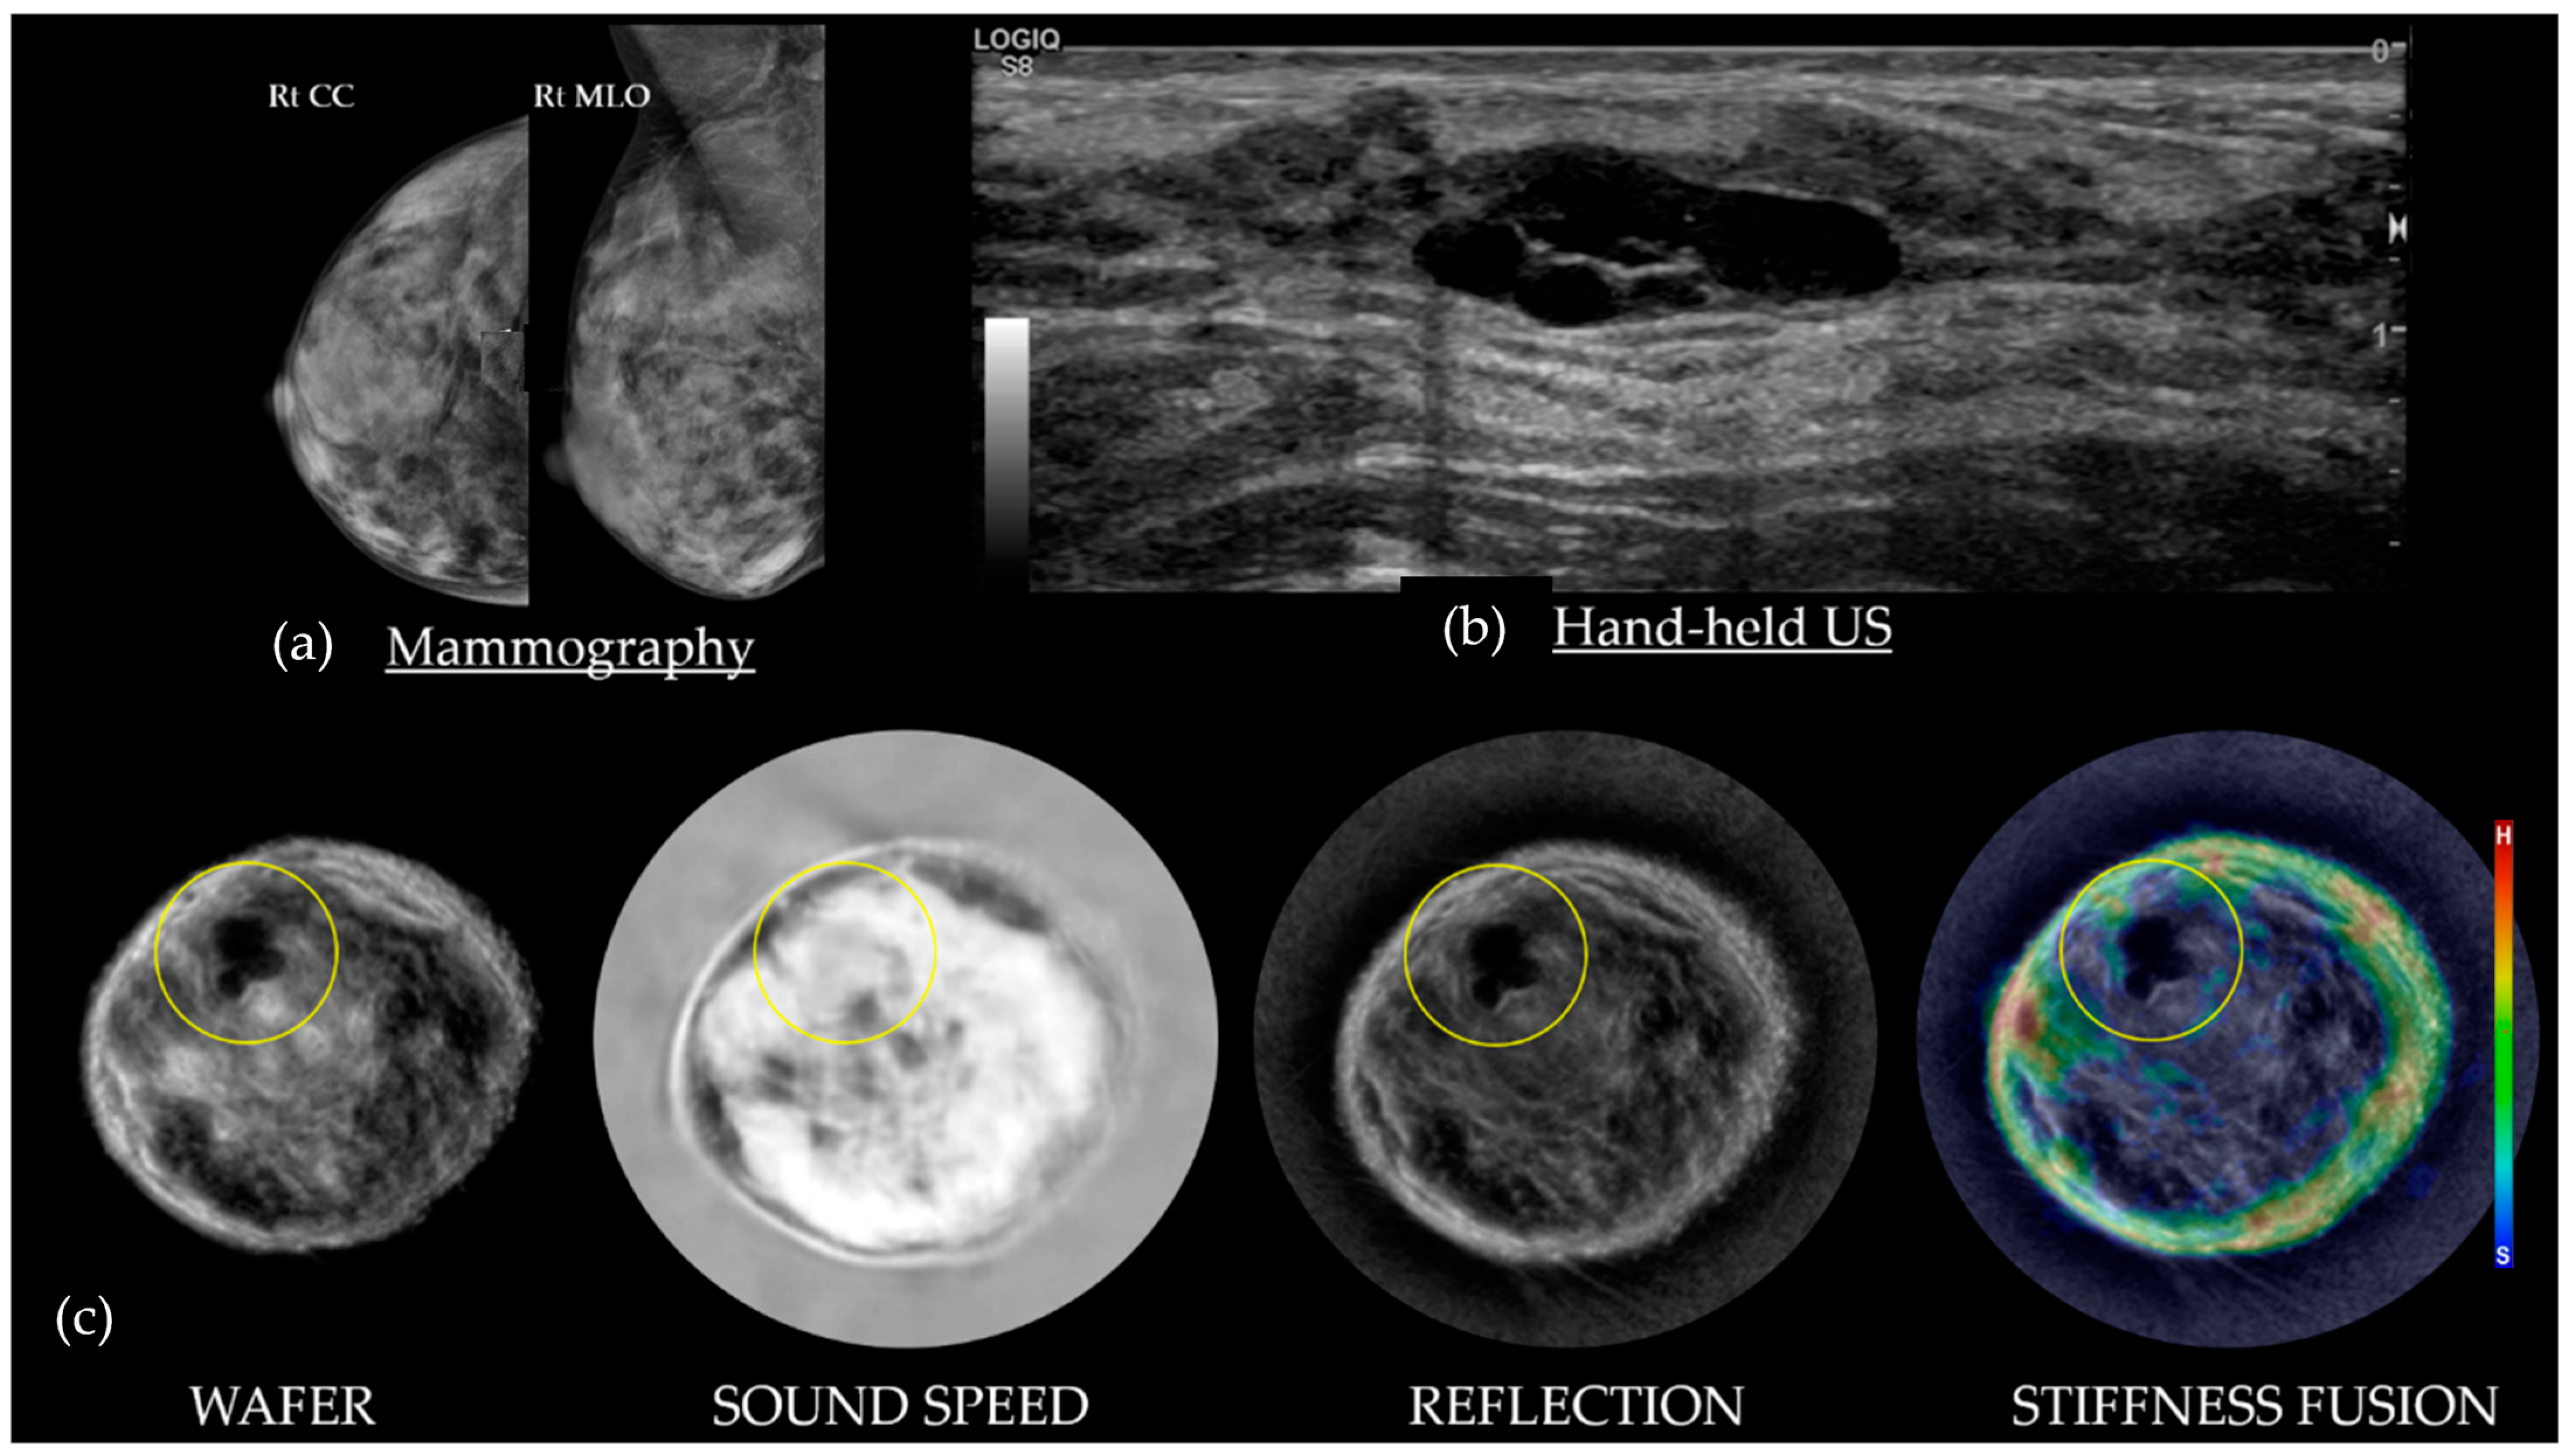

3.1. HHUS Reflection vs. SoftVue Reflection

3.2. SoftVue Sound Speed

3.3. SoftVue WAveForm Enhanced Reflection (Wafer)

3.4. SoftVue Stiffness Fusion